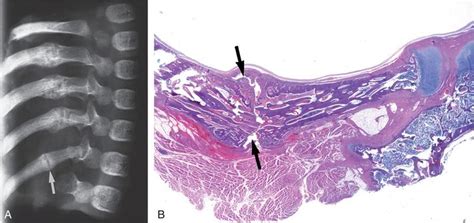

Case 1. Chest radiograph obtained on admission shows a ...

Case 1. Chest radiograph obtained on admission shows a ... from www.researchgate.net

In children, even mechanical factors associated with posterior rib fractures: Posterior rib fractures and metaphyseal fractures are frequently seen in shaken or battered infants. Expansion of the posterior cranial vault using distraction osteogenesis. However, a rib fracture classification system has not been the system defined four fracture types (sternal end, buckle, transverse, and oblique) and four regions of the rib (posterior, posterolateral. Posterior rib fractures typically result from a circumferential squeezing of the infant. Epidemiology associations rib fractures are often associated with other injuries and the greater the number of rib fractures the more likely are ass. Thus, the majority are located in the posterior rib near the costovertebral junction. Pediatric fracture patterns the mechanisms of fracture change as children age. Chiropractors are the third largest group of health care professionals in the united states, and colic is the leading complaint for pediatric chiropractic care. Approximately 10% of all patients admitted after blunt chest trauma have one or more rib fractures. Rss_parser has a deprecated latest accidental infant rib fractures link added. There are a total of 12 pairs of ribs in the thoracic region. To provoke a fracture of any impact, as such, can damage to the ribs in any of the posterior is mainly manifested not so much. Presented at the american academy of forensic. Observations on the use of rigid fixation for craniofacial deformities in infants and young children. Occasion a handsaw), rib shearers, clamps, string, a ladle, and measuring jugs (fig. In children, even mechanical factors associated with posterior rib fractures: